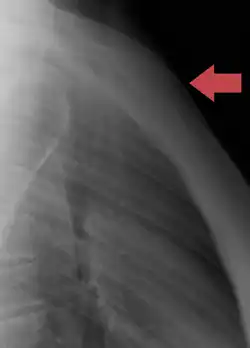

Traumatologie

Les fractures du sternum sont plutôt rares. Elles peuvent résulter d'un traumatisme, par exemple lorsque la poitrine d'un conducteur est forcée dans la colonne de direction d'une voiture lors d'un accident de la route. Une fracture du sternum est généralement comminutive. Le site le plus courant des fractures sternales se situe à l'angle sternal. Certaines études révèlent que des coups de poing répétés ou des coups continus dans la région du sternum ont également causé des fractures, comme dans des sports de contact comme le hockey et le football. Les fractures du sternum sont fréquemment associées à des lésions sous-jacentes comme des contusions pulmonaires[7].

Une luxation manubrio-sternale est rare et peut se produire dans des situations équivalentes à la fracture. Elle peut être favorisée par la présence d'arthrite[8].